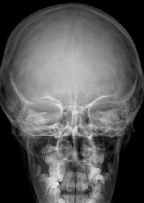

PA SKULL PROJECTION

Posteroanterior • Frontal view • Evaluation of cranial and facial structures

Visible Anatomical Structures

Frontal Bone

Complete frontal region

Crista Galli

Ethmoidal process

Ethmoidal Cells

Posterior ethmoidal

Petrous Bones

Temporal petrous portion

Temporal Bones

Temporal bones

- Frontal sinuses - Frontal sinus cavities

- Eye orbits - Complete orbital borders

- Optic foramina - When included

- Cranial sutures - Coronal, sagittal, lambdoid

- Diploe - Cranial spongy bone